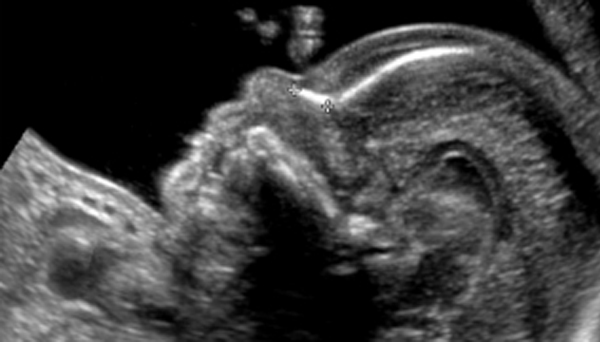

3D/4D Ultrasonography

Our 3D/4D Ultrasonography service offers detailed, real-time imaging of your baby, providing a unique view of fetal development. With high-resolution, moving images, this service enhances prenatal care and creates memorable bonding experiences.

Growth Scan

Our Growth Scan service offers detailed ultrasound assessments to monitor fetal growth and development throughout pregnancy. With precise measurements and expert analysis, we ensure the health and well-being of both mother and baby